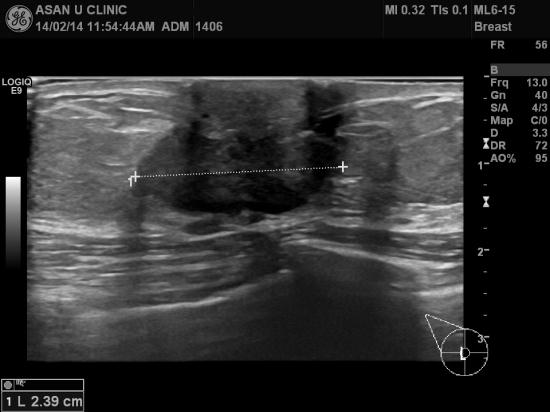

건강검진상 유방에 이상소견있다고 조직검사 의뢰되신

65세 여성분입니다.

내원당시 우측 유방 유두하부에 만져지는 혹과 상외부에

만져지는 1cm전후 크기의 결절이 있었으며

우측 겨드랑이 또한 림프절의 비대가 촉지되는 상태였습니다.

초음파를 시행하여 세개의 혹들이 모두 악성결절의심되어

조직검사 시행하였으며

유방의 두개의 혹은 침윤성 유방암,

우측 겨드랑이의 혹은 전이된 림프절로

진단되었읍니다.